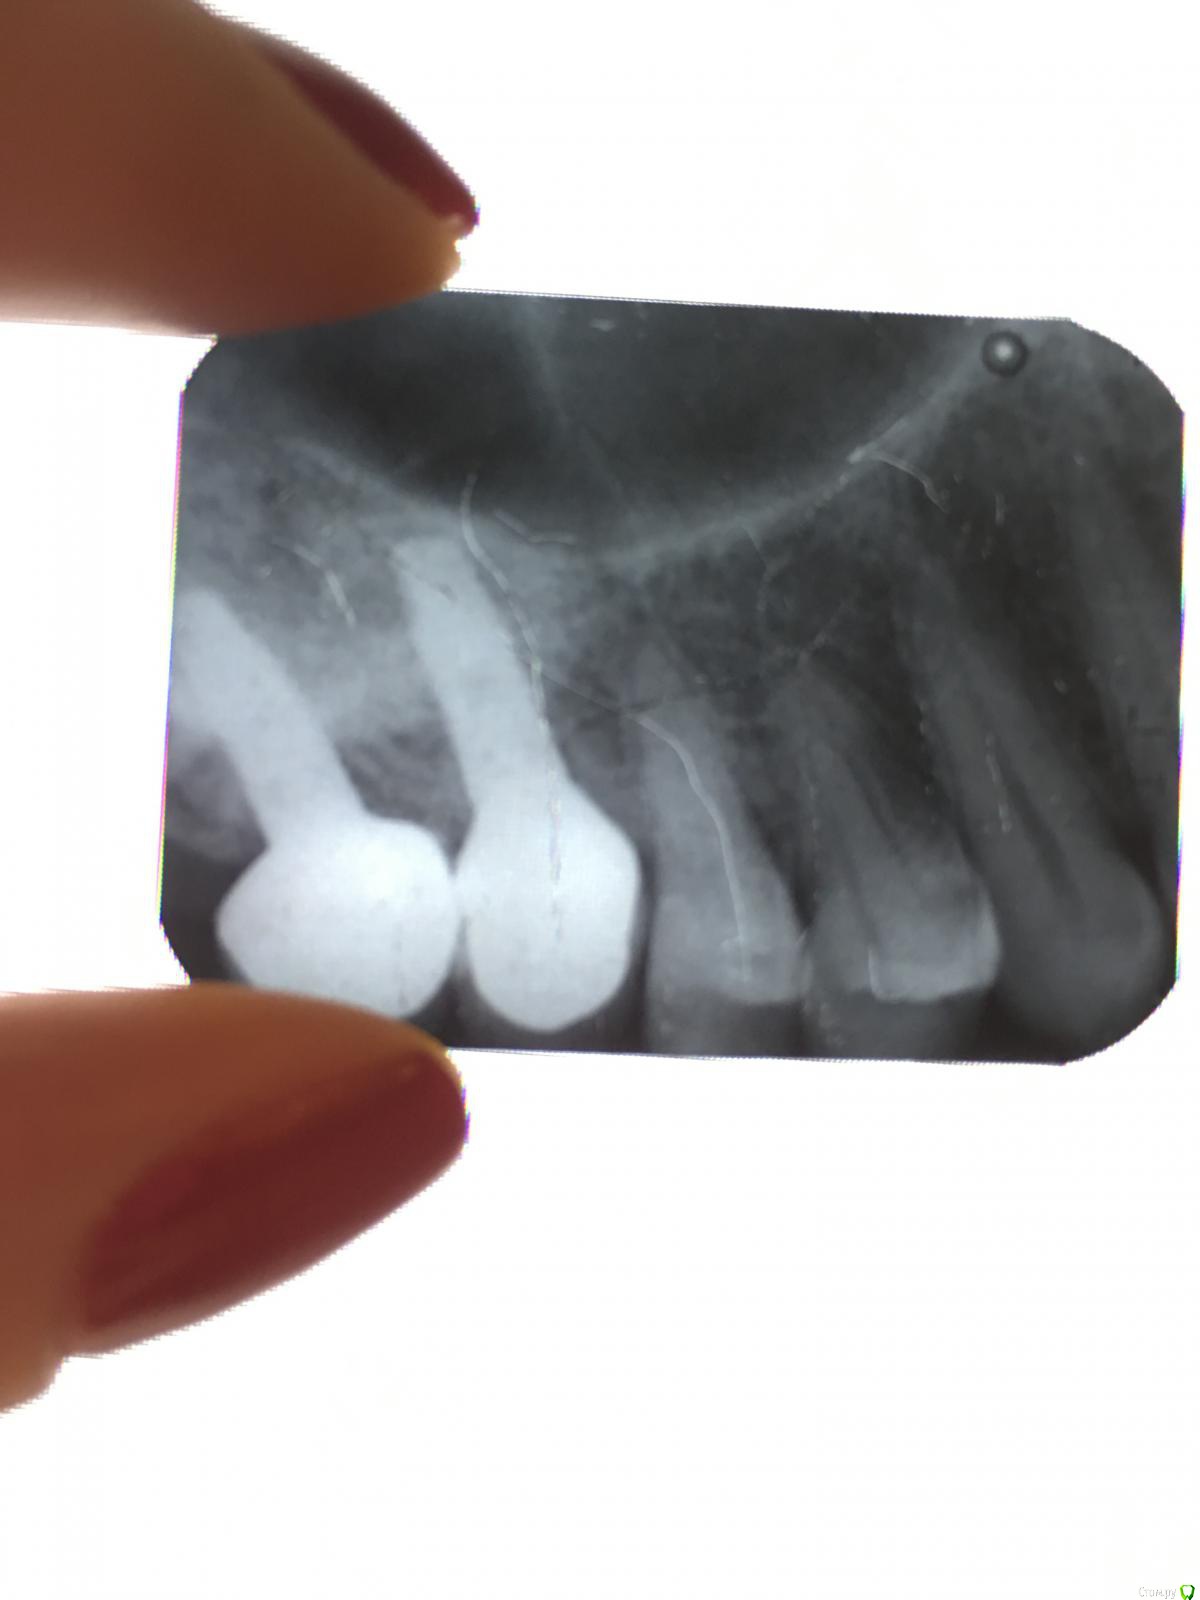

Ольгаxxx Опубликовано 16 февраля, 2019 Поделиться Опубликовано 16 февраля, 2019 (изменено) Здравствуйте. Ситуация такова. Месяц назад был приобретен ирригатор, у самой установлены имплантаты на верхей челюсти слева, 6 и7ка. Вчера вечером было обнаружено, что скорее всего из-за ирригатора и струи воды что-то случилось с цементом и коронка стала шататься(((. Снимок прилагаю.Вопросы:-обращаясь в клинику, где устанавливала импланты, могут ли мне поставить на место металлокерамич. коронку? Или нужно будет новую делать?-это стоит каких-то денег, если врач посадит ее на место? Если можно какая цена такой процедуры? (звонить в клинику буду в понедельник), но хотелось бы понять, чего ждать(.-идет ли инфицирование, если коронка потеряла герметичность из-за цемента?Спасибо, если поможете. Изменено 16 февраля, 2019 пользователем Ольгаxxx Ссылка на комментарий